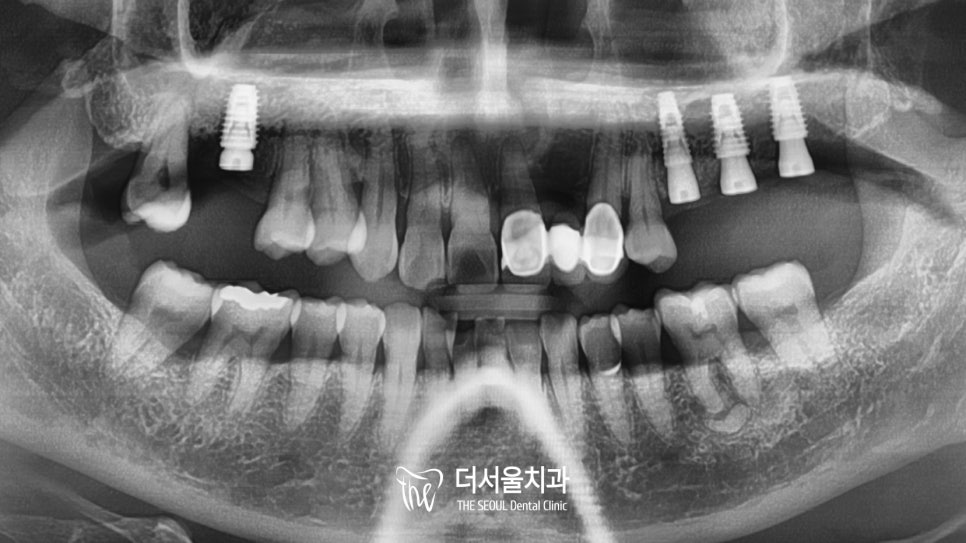

타원에서 9개로 진단을 받았던 환자 분,

더서울에서는 단 4개의 식립을 진행했습니다^^

무절개로 진행하여

출혈이 단 한방울도 나지 않았는데요.

파노라마를 확인해보면 알맞은 각도와 형태로

튼튼하게 심어져 있는 것을 볼 수 있는데요.

골융합이 단단하게 진행되고 나서

최종보철을 올려드리기로 했습니다.